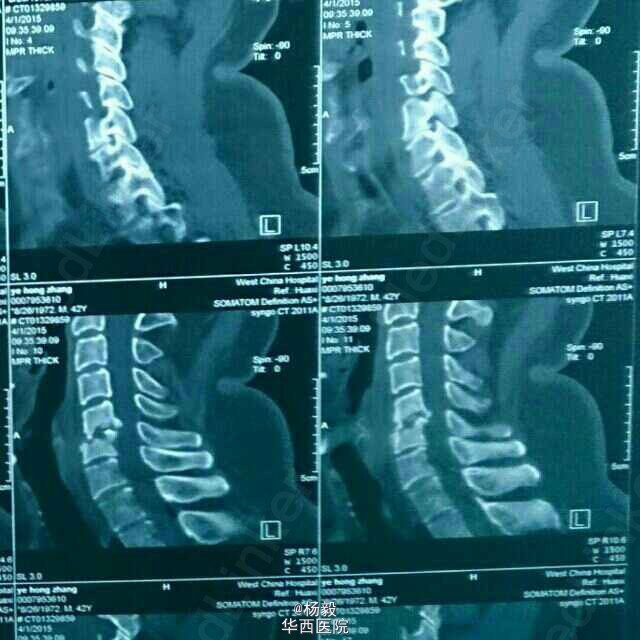

患者男性,47岁,因颈部疼痛在外院行射频消融手术,术后疼痛加剧,来我院就诊,急查血沉c反应蛋白,血常规。炎性指标上升,ct显示骨质破坏,终板炎。嘱戴颈托,制动,对症保守治疗。2个月复查。记得一个月以前一例类似病例,还在和医院打官司,法医鉴定。